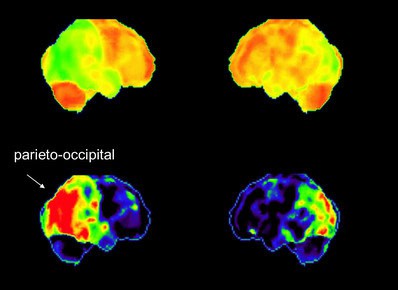

Mittels DaTScan kann auch eine Levy-Body-Demenz (DLB) nachgewiesen werden, eine Parkinson-verwandte Erkrankung, bei der die geistigen Beeinträchtigungen noch vor den motorischen Störungen auftreten. Andere Demenzformen, wie die Demenz vom Alzheimer-Typ und die frontotemporale Lobärdegeneration (M. Pick), lassen sich bereits im Stadium des Mild Cognitive Impairments (MCI) erkennen. Die hierbei vorhandenen leichten kognitiven Störungen äußern sich durch Gedächtnisstörungen, Lernschwierigkeiten, Konzentrationsstörungen und schnelle geistige Ermüdung. Mittels Hirnperfusionsszintigraphie lassen sich bei den betroffenen Personen mit Alzheimer oder Pick-Demenz typische Durchblutungsstörungen nachweisen.